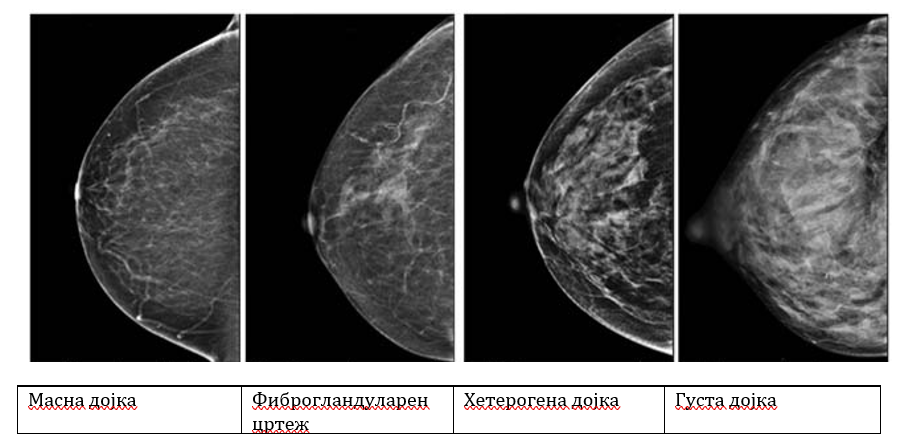

Густина на дојки

Густина на дојка е поим кој се користи во мамографијата за да опише колку жлездено и сврзно ткиво има во дојките во однос на масното ткиво. Тоа не се чувствува со рака, туку се гледа само на мамографска слика.

Што значи "густа дојка"?

• Дојките се „густи“ кога има повеќе жлездено и сврзно ткиво, а помалку масно ткиво.

• На мамографијата, густото ткиво изгледа бело, исто како и потенцијалните несакани промени (како тумори). Затоа е потешко да се забележат абнормалности кај жени со густи дојки.